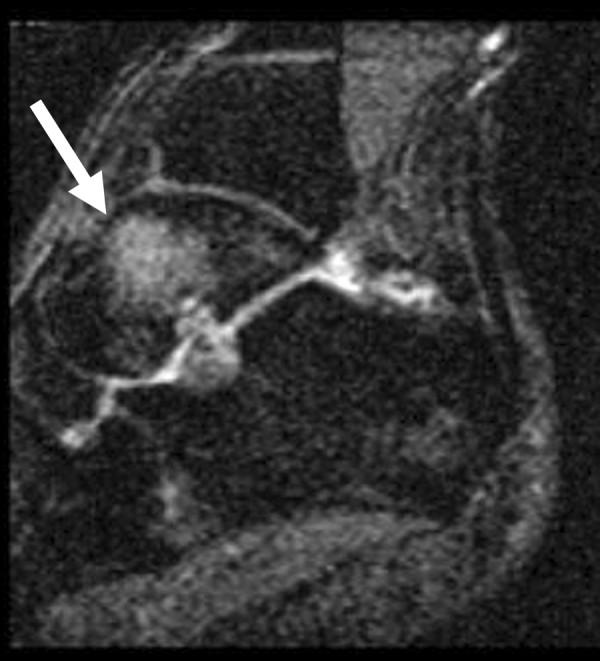

Bone marrow edema was seen only in the talus, and was a common finding, observed in nine of the twelve ankles imaged (75%) and was associated with pain in all cases. On fluid-sensitive sequences, bone marrow edema was ill-defined and centered in the talar neck or body, although in three cases it extended to the talar dome. No apparent gender predilection was noted. No occult stress fracture could be diagnosed. A moderately strong correlation (phi = 0.77, p= 0.0054) was found between edema and pain in the study population.

仅在距骨中发现骨髓水肿,这是一个常见的表现,在12个成像踝关节中的9个(75%)观察到,并且在所有病例中均与疼痛相关。在液体敏感序列上,骨髓水肿边界不清,集中在距骨颈或距骨体,尽管在3例中延伸至距骨穹窿。未发现明显的性别倾向。未诊断出隐匿性应力性骨折。在研究人群中,水肿与疼痛之间存在中度强相关性(phi = 0.77,p = 0.0054)。